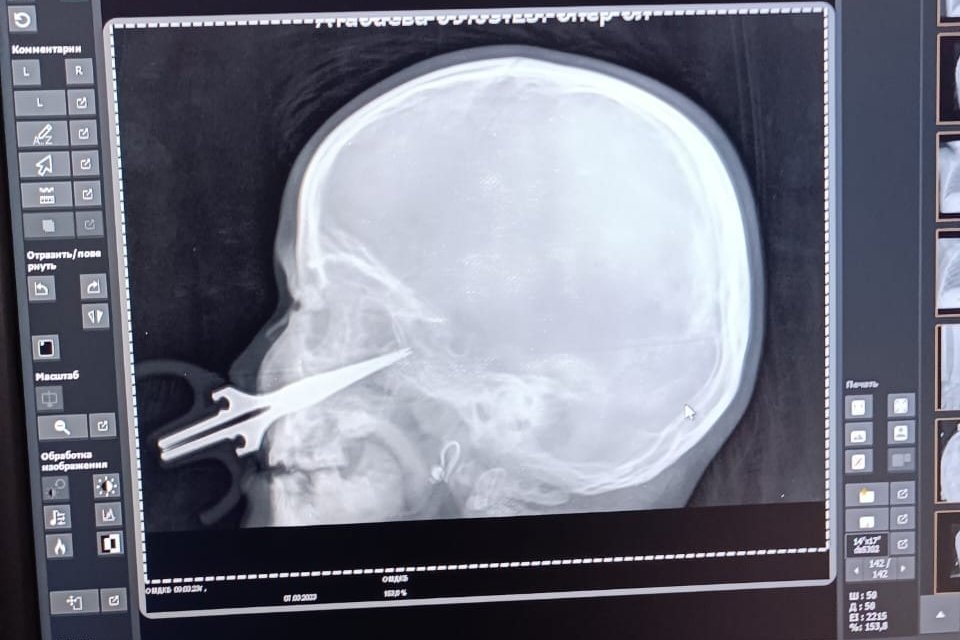

Do dramatu doszło w Kirgistanie. 5-letnie dziecko bawiło się w domu nożyczkami. W pewnym momencie spadła ze stołu i upadła, nadziewając się na ostrą część przedmiotu. Nożyczki wbiły się dziecku w twarz przez policzek na głębokość około 7 centymetrów. Przez zatokę szczękową dotarły aż do czaszki dziecka.

Rodzice przywieźli córkę do Międzyregionalnego Szpitala Dziecięcego w Osz w czwartek 9 marca. O zdarzeniu poinformowało kirgiskie Ministerstwo Zdrowia. Dziecko trafiło do szpitalnego oddziału otolaryngologii, który zajmuje się urazami głowy i szyi.

Lekarze postanowili wykonać operację pod kierownictwem szefa oddziału Umutbeka Pazyłowa. Na szczęście udało się usunąć dziewczynce nożyczki z twarzy.

"Okoliczne duże tętnice nie zostały naruszone, w przeciwnym razie życie dziecka byłoby poważnie zagrożone. Stan dziecka jest dobry, dziewczynka jest przygotowywana do wypisu ze szpitala" – przekazało ministerstwo w komunikacie w poniedziałek 13 marca.